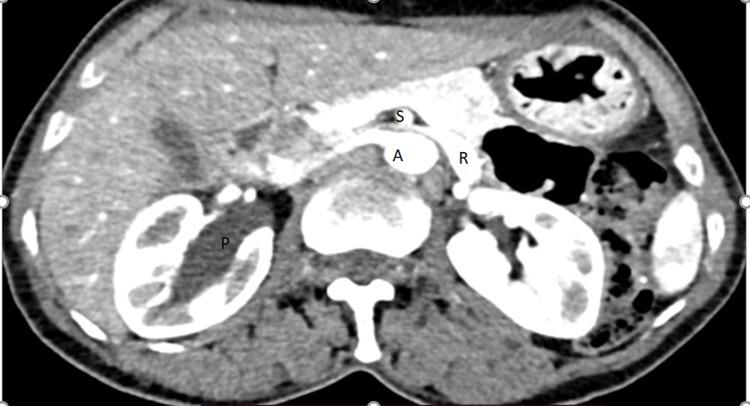

病例报告;同时合并左胡桃夹综合征和右肾盂输尿管连接处梗阻

Case Report; Concomitant Left Nutcracker Syndrome and Right Ureteropelvic Junction Obstruction.

We report rare case of concomitant left nutcracker syndrome and right ureteropelvic junction obstruction (UPJO) on adult female patient diagnosed by CT urogram after she presented with intermittent bilateral flank pain. For this we did Anderson-Hynes pyeloplasty for right ureteropelvic obstruction, it was laparoscopic initially but due to difficulty of stenting it is changed to open. She had smooth post-op course then discharged on 3rd post-op day. Symptoms of nutcracker syndrome are not that much bothersome for the patient so we planned to follow her conservatively.

摘要